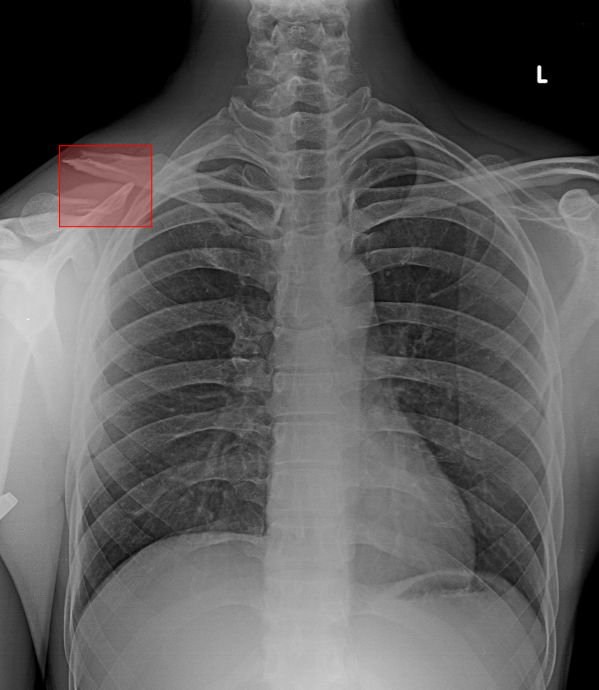

What does AI-detected pathology look like?

Eight examples of AI-annotated chest X-rays with color-coded pathology overlays

Chest X-ray with AI-detected Pneumothorax highlighted

Pneumothorax